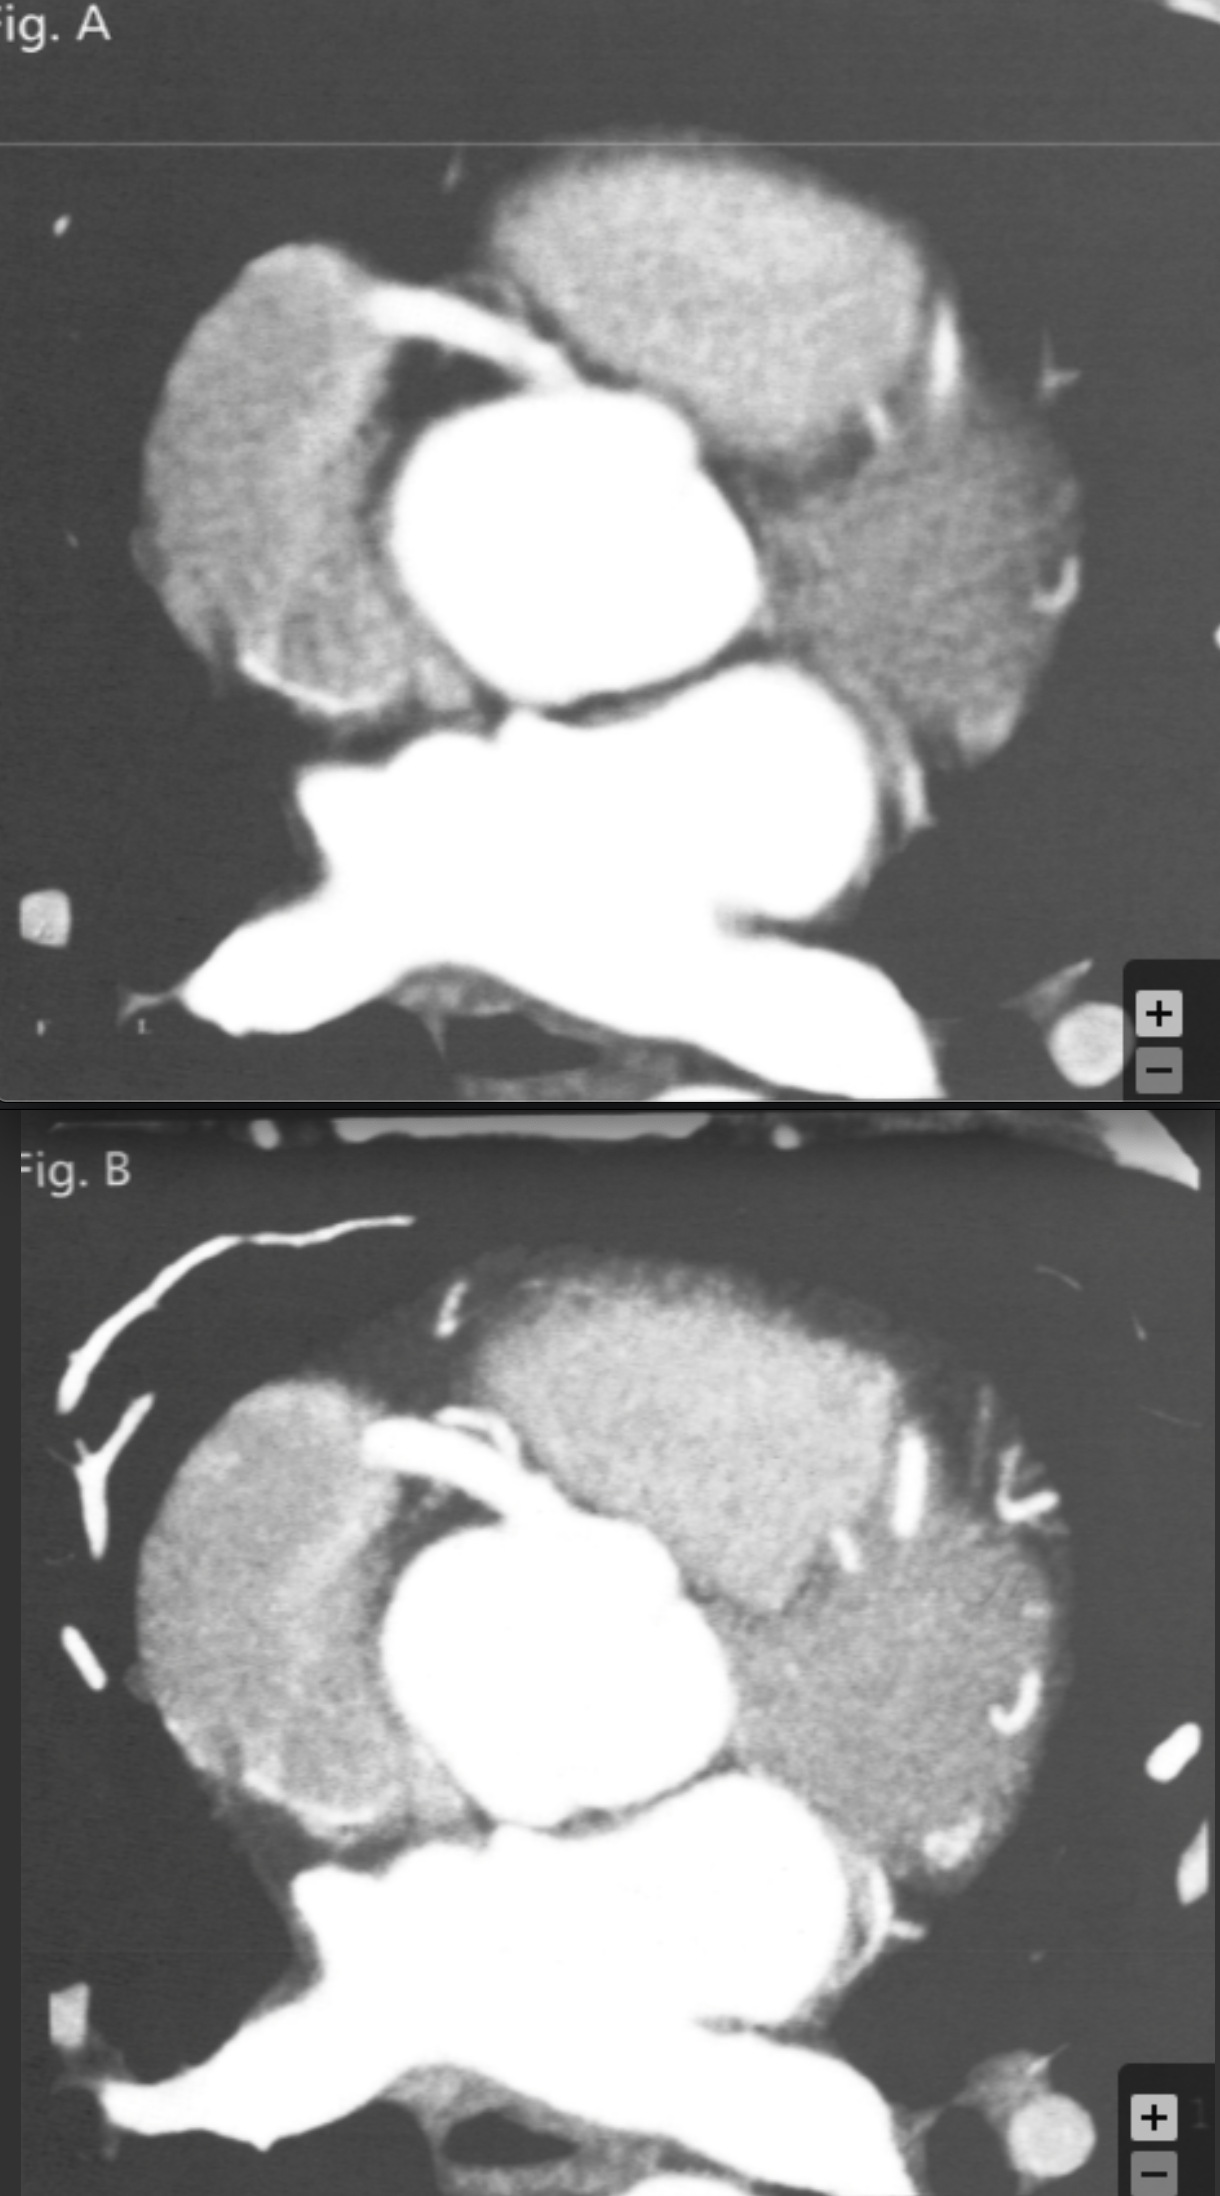

Based on the comparative appearance of these two images, what element of the reconstruction was modified during the second reconstruction?

Slice Thickness

Describe why slice thickness is so important in regards to coronary imaging